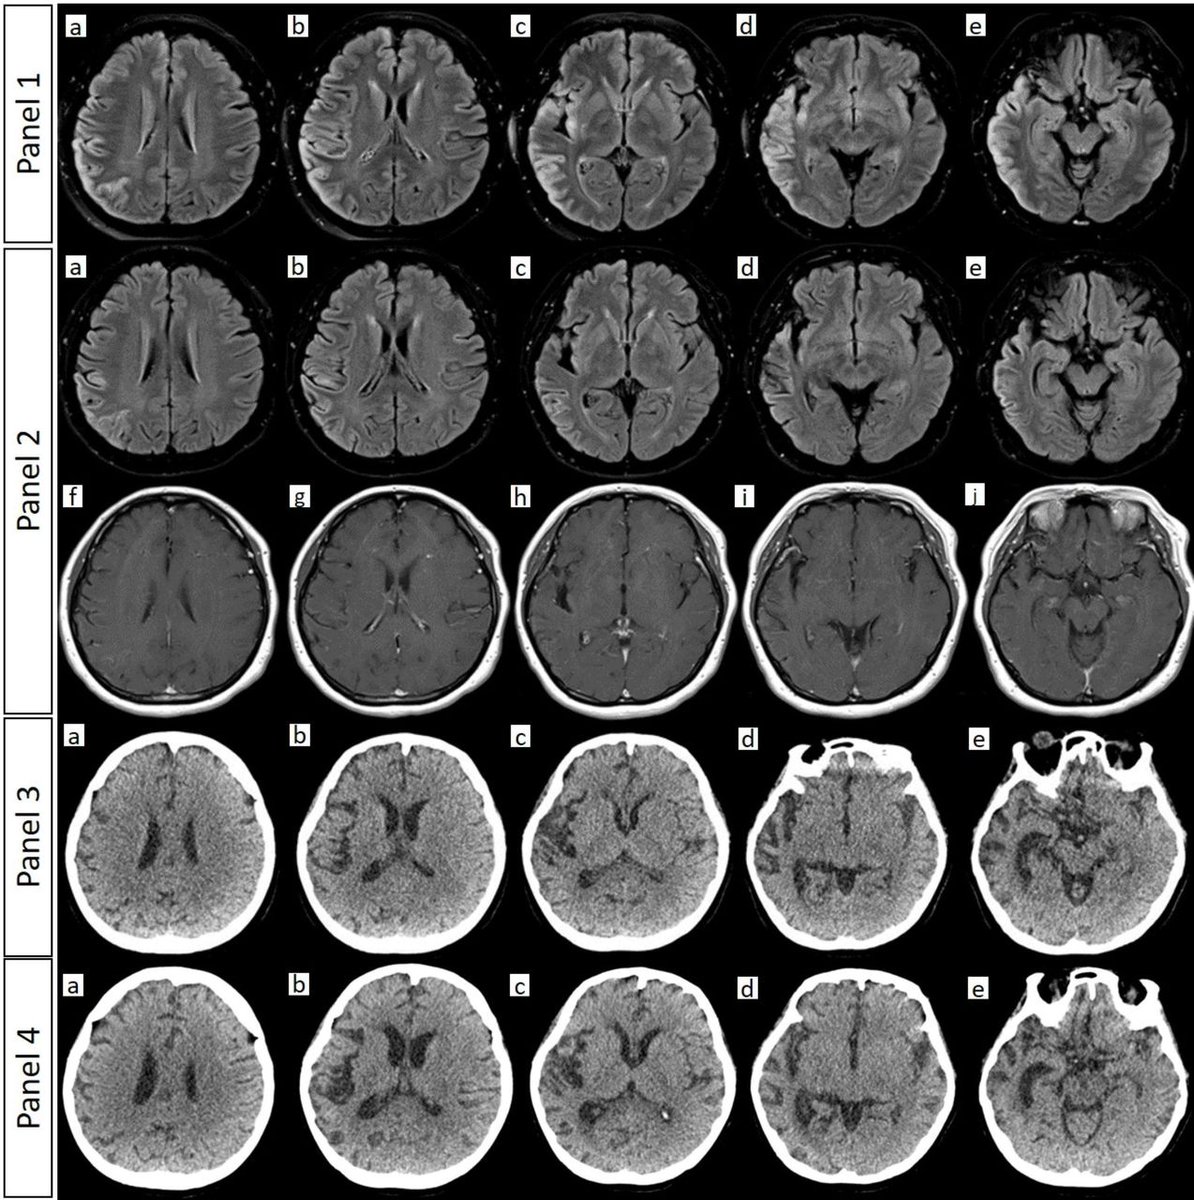

š§ Fentanyl misuse can cause CHANTER syndrome: Cerebellar, hippocampal and basal nuclei transient oedema with restricted diffusion. Thereās a characteristic MRI pattern: restricted diffusion in the basal ganglia and hippocampi, with cerebellar oedema and haemorrhage. š Open